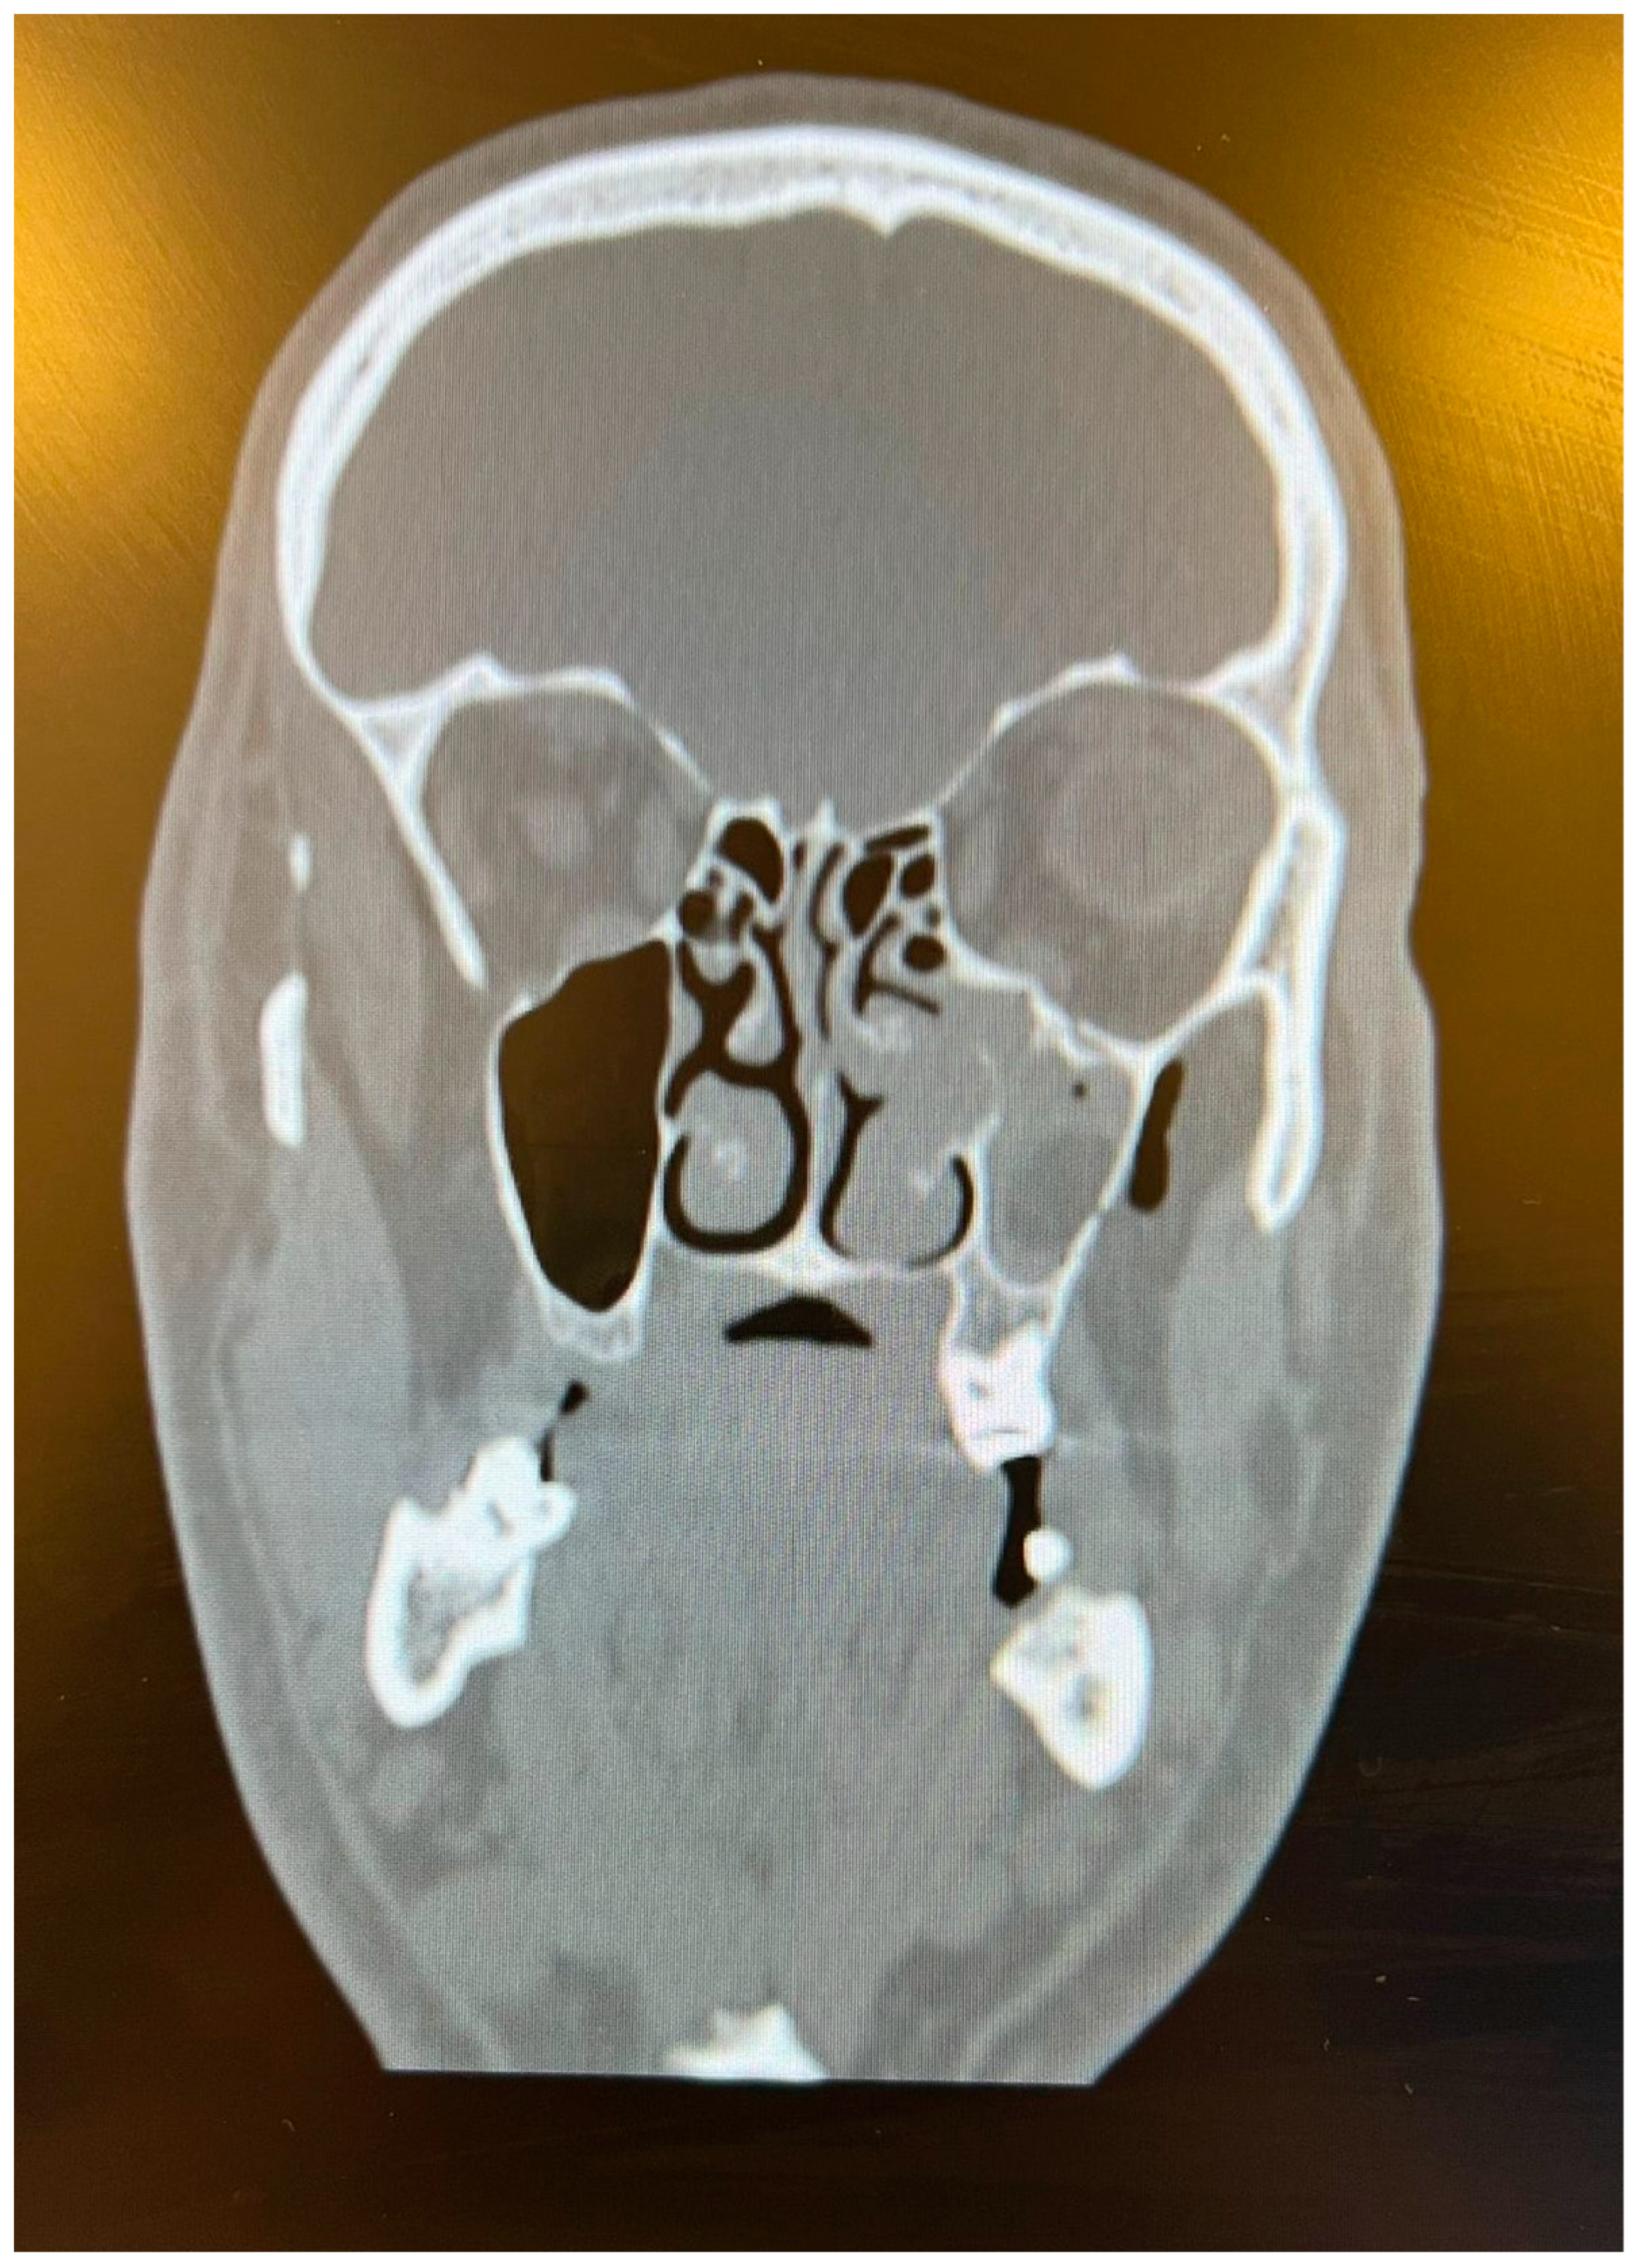

As plastic surgeons, we observed that there were not only hand injuries but also maxillofacial traumas. During the Eid al-Adha period, the number of people traveling between cities increases, which leads to an increase in traffic accidents. In the literature, it was previously reported that being on vacation plays a role in crash severity [14]. A total of 25 patients with maxillofacial trauma were enrolled in our study. Notably, 40% of the patients had orbital floor fractures, which represent the most common injury type (Figure 3). This fracture was caused by the impact of an injuring agent incapable of transitory deformation, such as traffic accidents, or the body part of an animal, which we encountered in two patients. Two out of thirty-six cases of animal kicks resulted in orbital fractures, which is a significant number and something that emergency services should take into consideration during this festival.

Figure 3.

A 38-year-old male who suffered an animal kick to his face. The CT scan shows a left-sided orbital floor fracture.